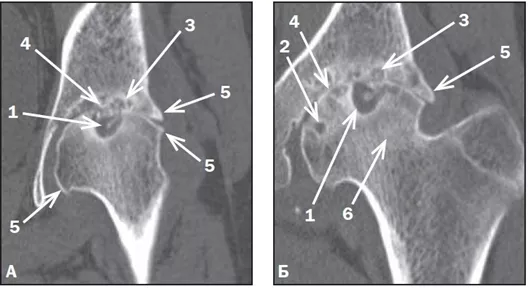

Рентгенография суставов. Изменения хрящевой и костной ткани имеются у большинства пациентов. При рентгенологическом обследовании через 2 года от дебюта болезни у 30% пациентов выявляется сужение суставных щелей, у 35% — эрозии, у 10% — нарушение роста костей. Ранние рентгенологические изменения развиваются в лучезапястных, тазобедренных и плечевых суставах. Через 6,5 лет у 39% пациентов выявляется сужение суставных щелей, у 64% — эрозии, у 25% — нарушение роста костей. При агрессивном течении сЮИА развивается анкилоз в лучезапястных и апофизальных суставах шейного отдела позвоночника, а также асептический некроз тазобедренных суставов (фото 14).

Фото 20 (А, Б). Коксартроз, осложнившийся асептическим некрозом головки бедренной кости при сЮИА. КТ, реконструкция во фронтальной проекции (А, Б). Асептический некроз головки бедренной кости (1). Отмечаются уменьшение в объеме и уплощение суставной поверхности бедренной головки с выраженной кистовидной перестройкой костной ткани головки (2) и подвздошной кости (3), чередующейся с участками субхондрального остеосклероза. На этом фоне определяется резкое сужение суставной щели с наличием признаков анкилозирования — участков, где суставная щель не прослеживается (4). Остеофиты на краях суставных поверхностей (5). Уплотнение костной ткани и укорочение шейки бедренной кости (6) [4].